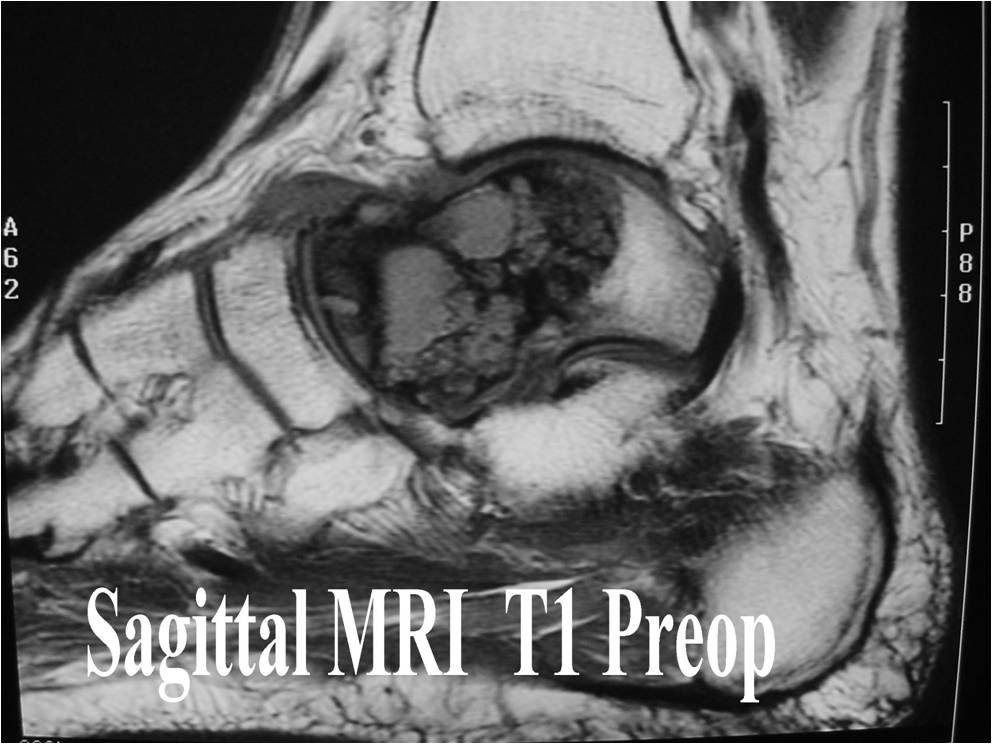

- (MRI appearance)

- Geographic, well circumscribed lesion in the epiphysis

- Intermediate Signal on T1

- High signal on T2 mixed with low signal areas (low signal areas proposed to be secondary to lysosomal content of highly cellular areas)

- Fluid/Fluid levels demonstrated in tumors that have undergone ABC change (aneurysmal bone cyst change)

- Extensive Surrounding edema is common

- Joint effusion in 30-50% of cases